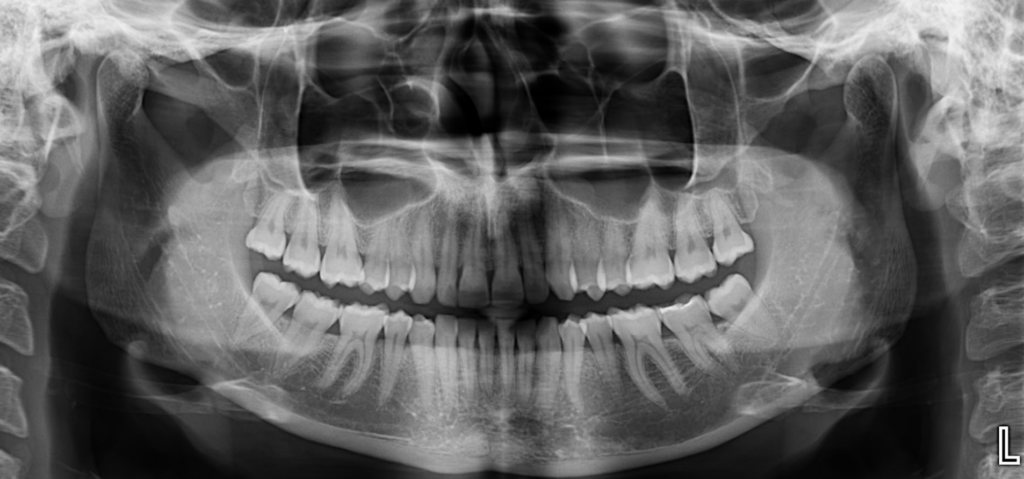

Radiografia Panorámica

A la evaluación de la radiografía panorámica se observa la neumatización de ambos senos maxilares, presencia de placa cervical mineralizada, pérdida de estructura coronaria incisal en piezas anterosuperiores y anteroinferiores y la restauración oclusal de la pieza 37.